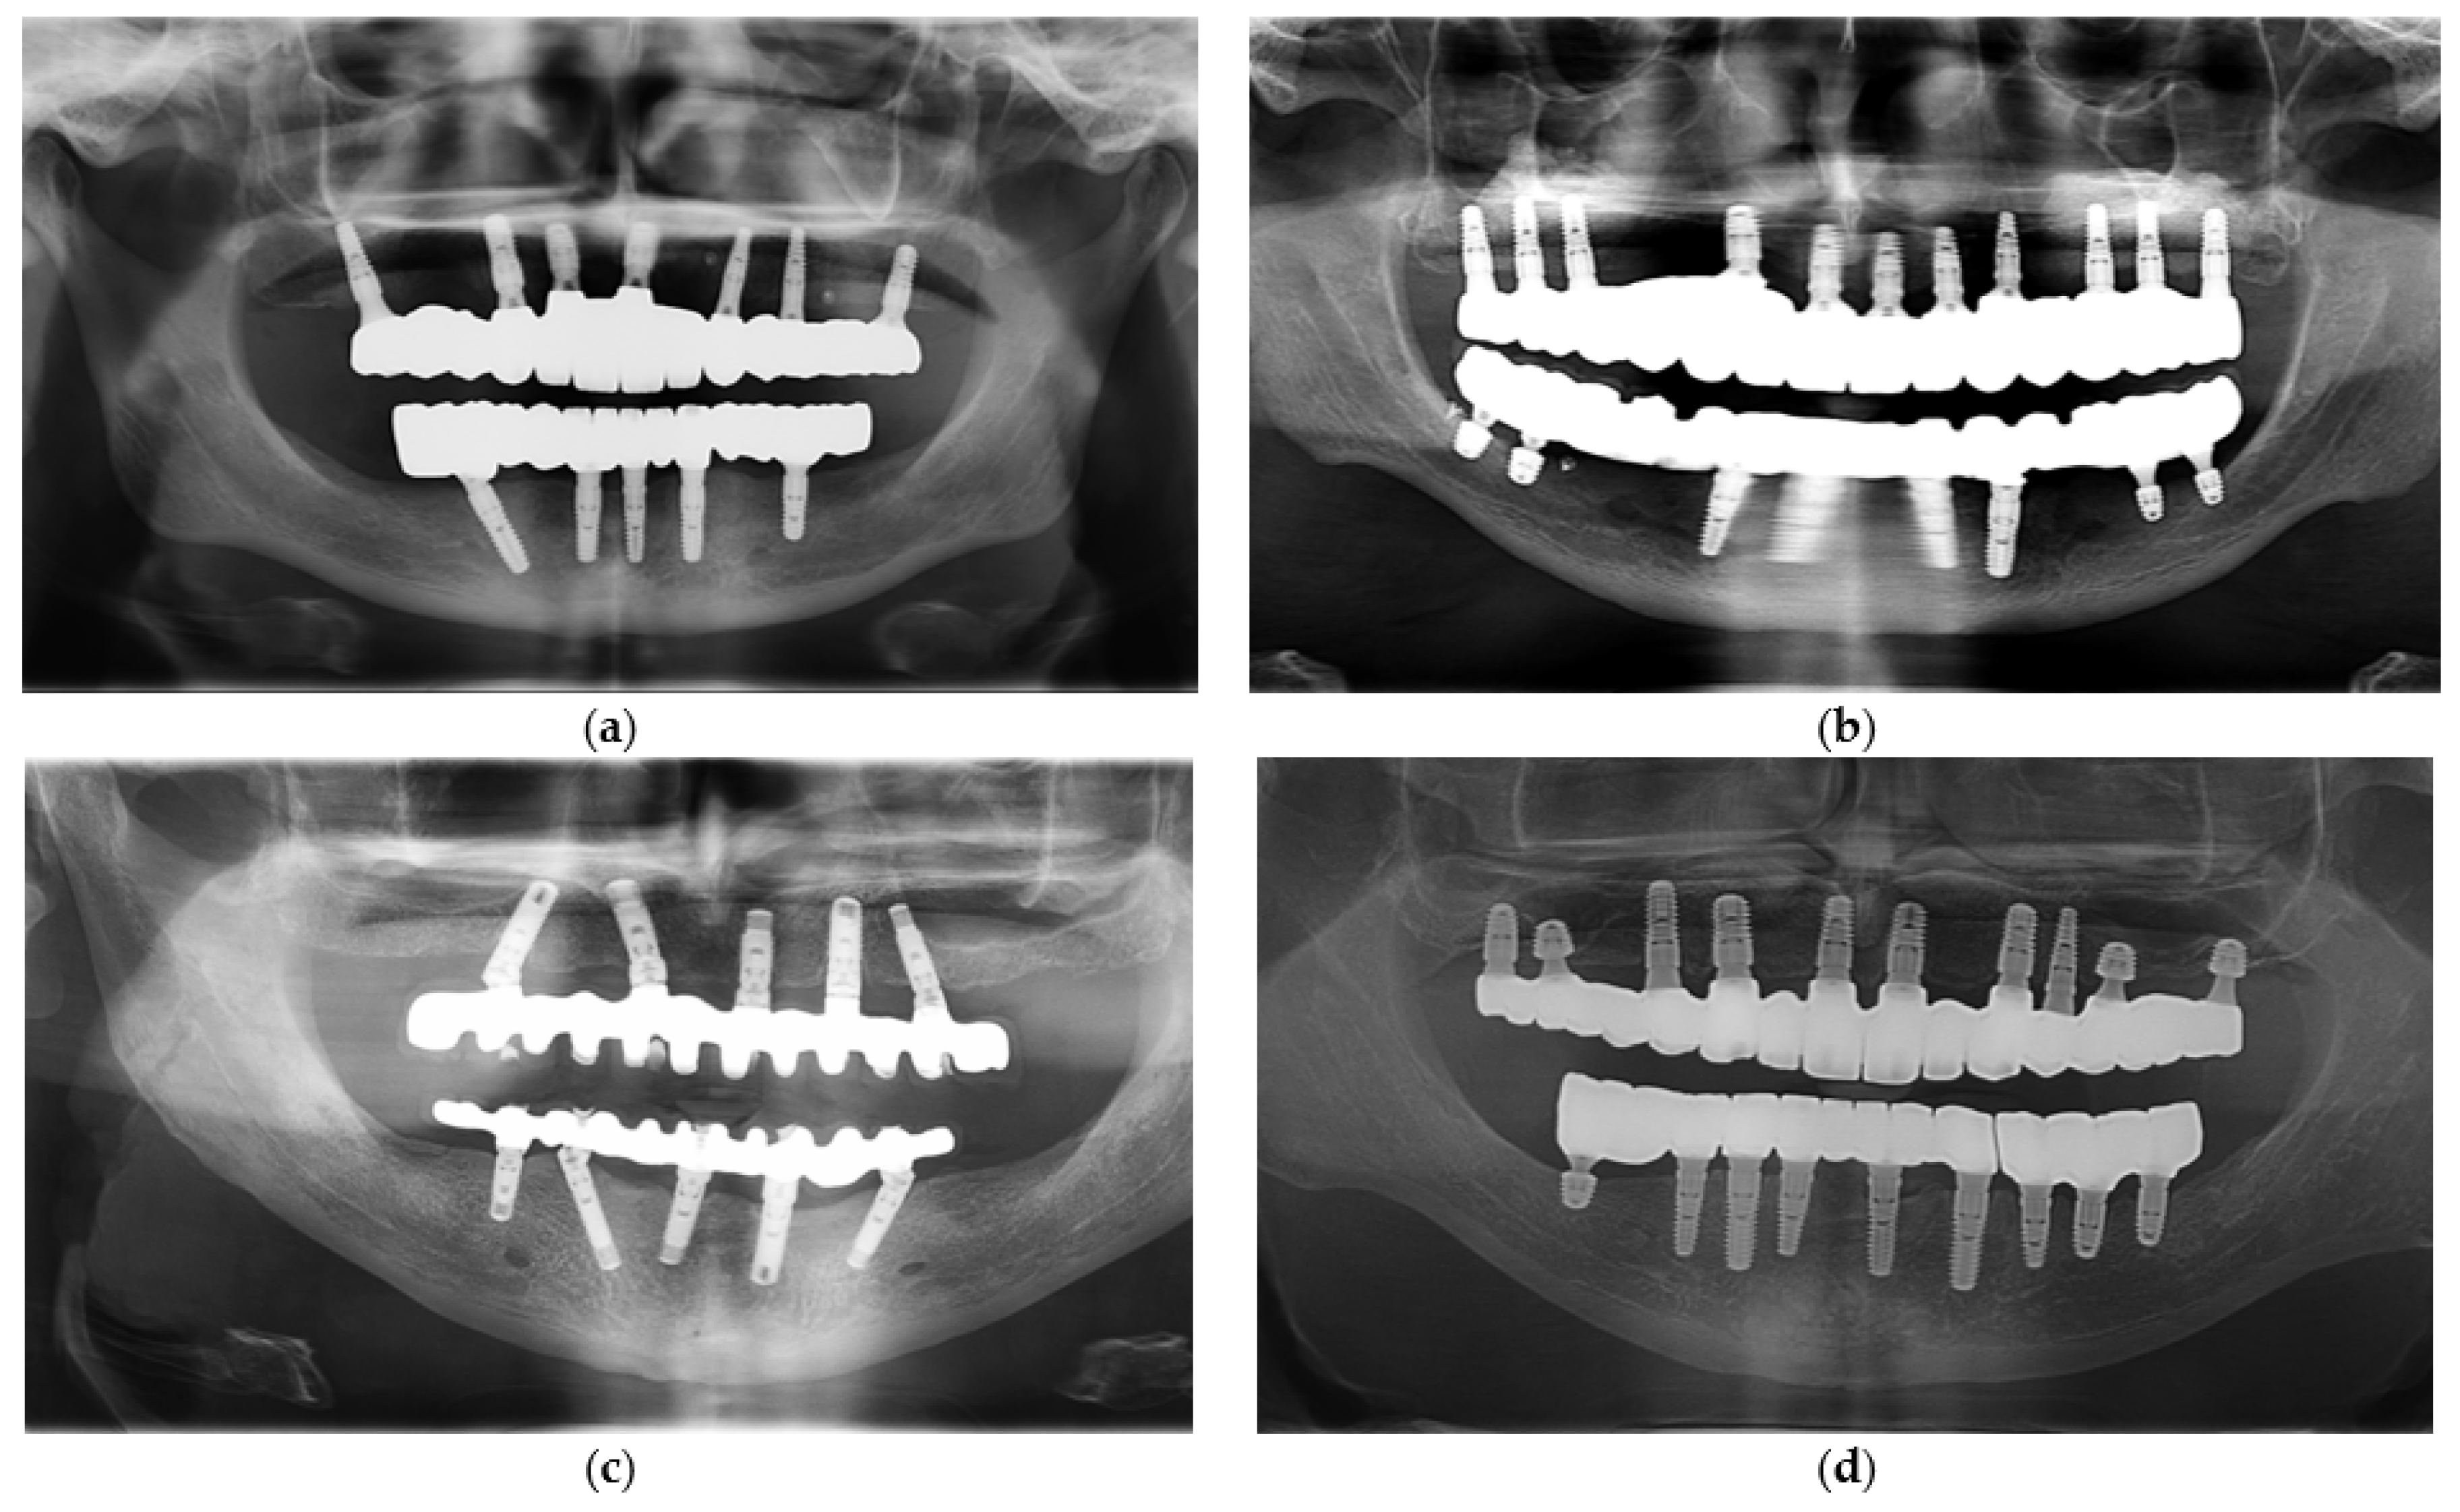

2.3. Prosthesis Fabrication Protocols

2.4. Data Collection and Outcome Measures

- Prosthetic framework complications—occurrence of framework fractures, deformation, or loss of integrity over time.

- Veneering ceramic complications—for hybrid metal–ceramic restorations, occurrence of chipping, delamination, or fracture of the veneering layer.

- Prosthetic gingiva adaptation—presence of soft tissue mismatch or loss of adaptation between the prosthetic gingiva and peri-implant soft tissues, documented through standardized frontal and lateral photographs.

- Mechanical retention issues—frequency of screw loosening or complete unscrewing events during the follow-up period.